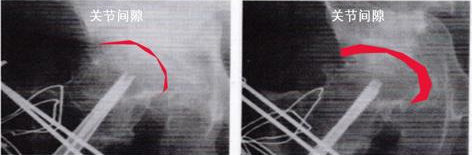

疗愈前(左)VS 疗愈后(右)

神经枝节末梢循环改善

改善血液循环:振动能促进局部和全身的血液循环及微循环。表现为接受疗愈后神经枝节末梢温度会明显升高,这正是循环得到改善、身体深度放松的标志。

疗愈后关节炎症消失